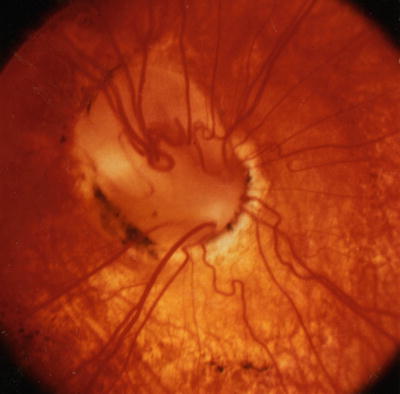

Papillorenal syndrome. The PARSA optic disc is characterized by perturbed angiogenesis, associated renal complications, sans a central retinal artery. Note central excavation with multiple cilioretinal vessels and absence of central retinal vasculature.

Color Doppler imaging has confirmed the absence of central retinal circulation in patients with papillorenal syndrome [286]. Visual acuity is usually 20/20 but may occasionally be severely diminished secondary to choroidal and retinal hypoplasia and, in some cases, to late-onset serous retinal detachments [286]. Peripheral visual field defects corresponding to areas of retinal hypoplasia are often present. The central optic disc excavation and peripheral field defects can simulate coloboma as well as normal-tension glaucoma. Follow-up examination has shown renal disease in some patients who were originally reported as having isolated familial autosomal dominant coloboma [286, 323]. In infants, the bilateral optic disc excavation can simulate congenital glaucoma, but the diagnosis can be established clinically by recognizing the characteristic optic disc morphology [217].